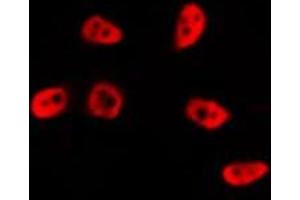

TP53 Reaktivität: Human WB, IF Wirt: Kaninchen Polyclonal RB08118 unconjugated

Produktnummer ABIN390201